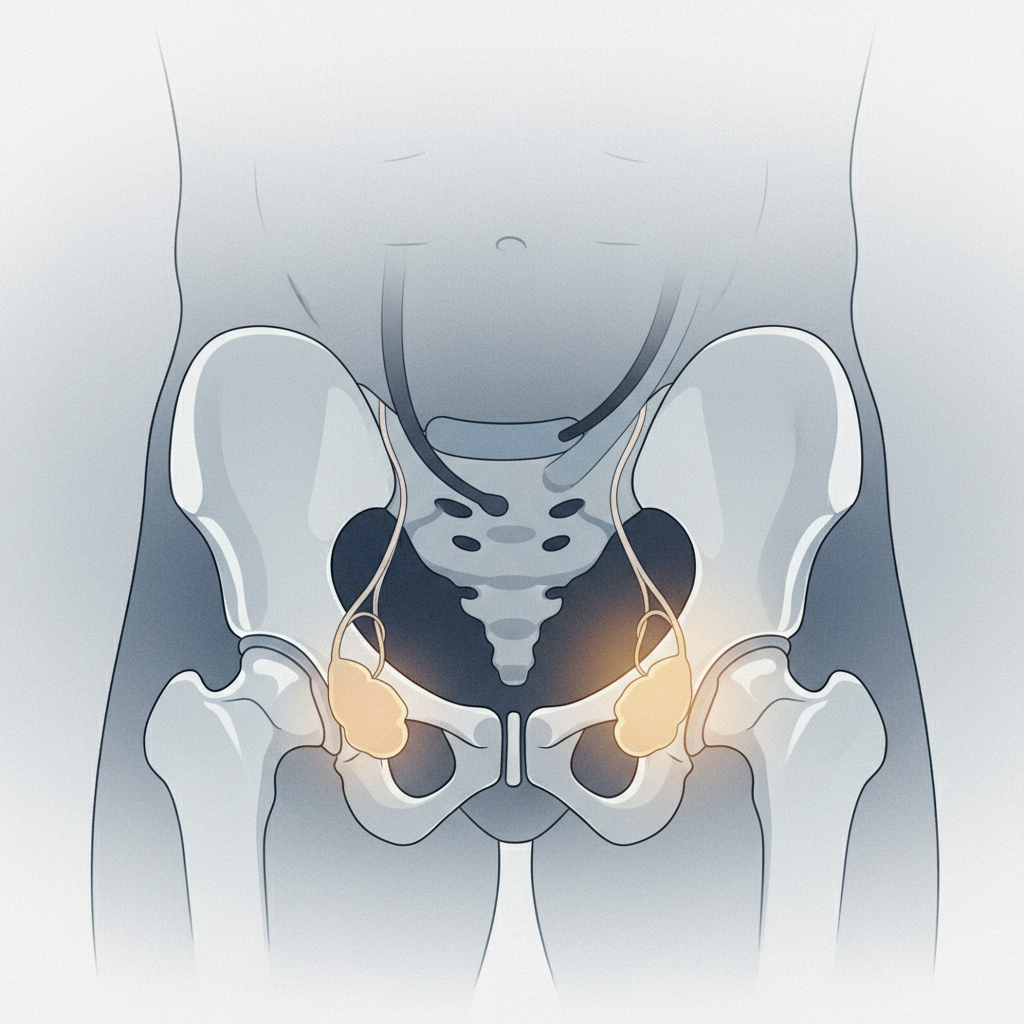

וריקוצלה (דליות האשכים) – ורידים מורחבים

וריקוצלה היא הרחבה של הוורידים המנקזים את הדם מהאשך, בדומה לדליות ברגליים. התופעה שכיחה יותר באשך השמאלי בשל מבנה אנטומי ייחודי. וריקוצלה עלולה לגרום לתחושת כבדות, אי נוחות או כאב עמום, במיוחד לאחר עמידה ממושכת או מאמץ גופני.

יתרה מכך, וריקוצלה היא אחד הגורמים המובילים לאי-פוריות הגבר, כיוון שהיא עלולה לפגוע בייצור ובאיכות הזרע. במקרים רבים, הטיפול יומלץ לגברים הסובלים מבעיות פוריות או מכאבים משמעותיים. הטיפול הוא ניתוחי ומטרתו לקשור את הוורידים המורחבים ולהפנות את זרימת הדם לוורידים תקינים.